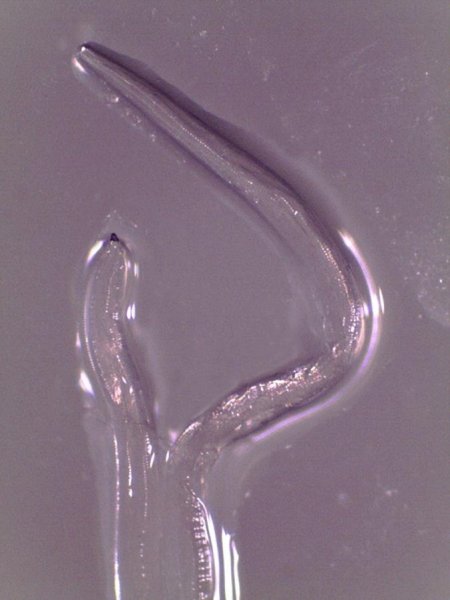

Фотография червя в глазу

В течение 20 дней из глаза Бекли вытащили 14 паразитов. Выяснилось, что это первый задокументированный случай, когда человек заразился червем Thelazia gulosa. Его переносят мухи вида Musca autumnalis, которые питаются слезами крупного рогатого скота.